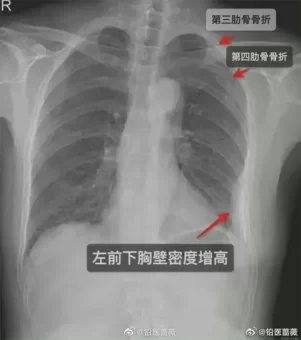

بعد خمسة أيام، اشتد الألم في صدر المرأة. فذهبت أخيرًا إلى المستشفى لإجراء فحص طبي والذي كشف أنها لم يكن لديها ضلع واحد، بل ثلاثة مكسور؛ اثنان على الجانب الأيمن من قفصها الصدري، وواحد على اليسار وهو ما جعلها تضطر إلى أخذ إجازة من العمل.